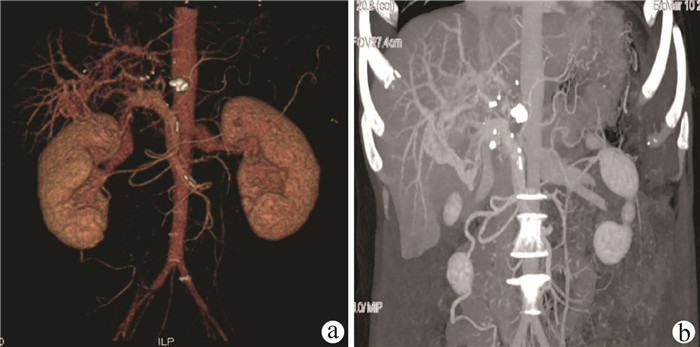

门静脉性胆道病1例报告

姜朋, 王树鹏, 刘亚辉

2022, 38(2): 430-432. DOI: 10.3969/j.issn.1001-5256.2022.02.034

摘要(724) HTML (240) PDF (2686KB)(54)

摘要: